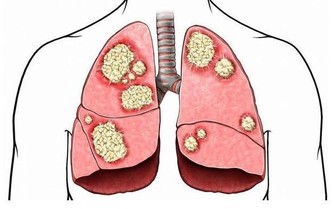

不分種族不分性別不分年齡,任何人都可能患上關節病。 關節病可以是膝關節直接受到衝擊或扭傷,也可以是關節骨和軟骨部分磨損、撕裂而引起。 炎症性關節病還可以由風濕性疾病引起,比如風濕性關節炎或系統性紅斑狼瘡,這些疾病導致的關節腫脹對關節的損傷是永久性的。